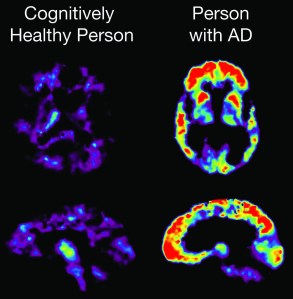

PET Scan showing PiB uptake –

Image courtesy of the National Institute on Aging/National Institutes of Health

Comparison of Healthy Brain to Brain affected by severe Alzheimer’s Disease